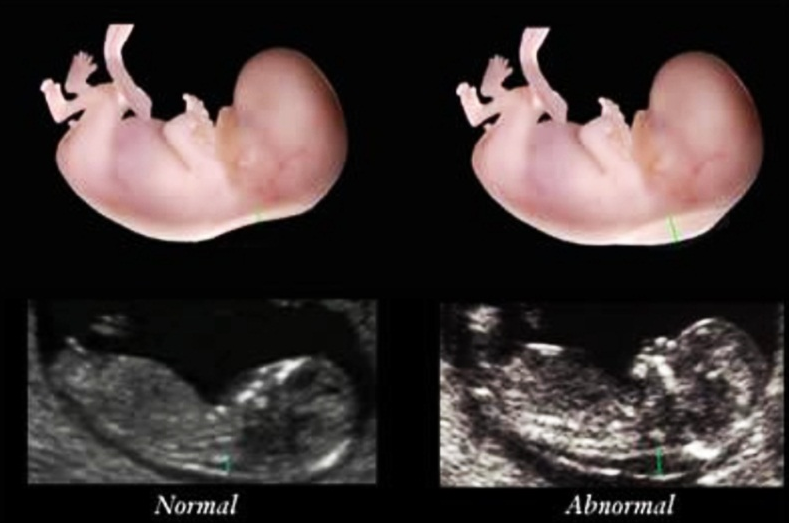

Thông thường, vào khoảng tuần thứ 18 và tuần thứ 22 của thai kỳ, mẹ bầu sẽ thực hiện siêu âm hình thái. Dựa vào một số dấu hiệu trên kết quả siêu âm, bác sĩ có thể chẩn đoán nguy cơ mắc hội chứng Down thai nhi như:

Vì sao bác sĩ lại chú ý đến chiều cao xương mũi của thai nhi? Nếu siêu âm thai nhi mũi tẹt thì có sao không? là thắc mắc của nhiều mẹ bầu. Tiêu chuẩn để giúp chẩn đoán, đánh giá nguy cơ mắc hội chứng Down thai nhi là dựa vào chiều cao xương mũi thai nhi. Nếu thai nhi không có xương mũi hoặc xương mũi của thai nhi quá ngắn thì rất có thể thai nhi đã bị mắc hội chứng Down. Vậy thai nhi bình thường sẽ có chiều cao xương mũi là bao nhiêu?

Bác sĩ sẽ xác định em bé đã có xương mũi hay chưa ở giai đoạn thai nhi được 12 tuần. Trường hợp siêu âm thai nhi mũi tẹt thì như thế nào? Phần lớn những trường hợp thai nhi 12 tuần tuổi không thấy xương mũi khi siêu âm thì nguy cơ cao là trẻ đã mắc hội chứng Down. Nếu sang tuần thai thứ 24, chỉ số chiều dài xương mũi thấp hơn so với tiêu chuẩn hoặc vẫn không đo được chỉ số này khi siêu âm thì nguy cơ này sẽ càng cao.